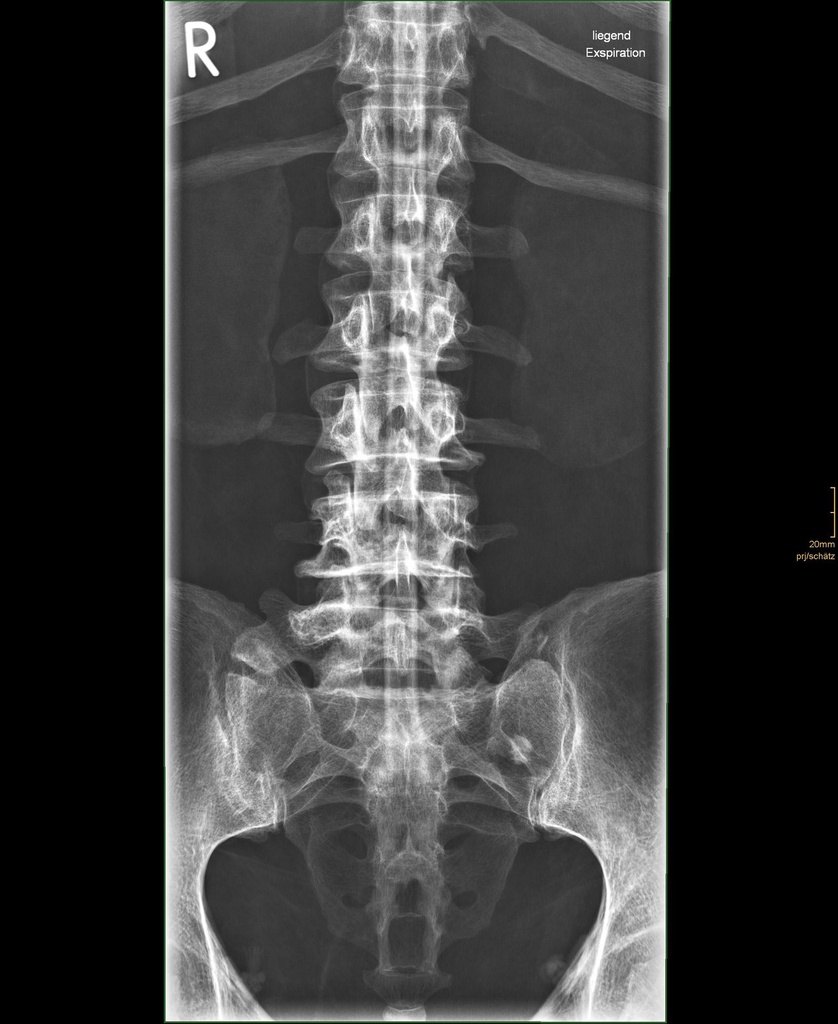

Dieses weltweit einmalige Phantom bietet erstklassige Übungsmöglichkeiten für die Lagerungs- und Einstelltechnik in der Projektions-Radiographie und gehört eigentlich zur Grundausstattung jeder Röntgen-Ausbildungsstätte. Das Phantom enthält ein natürliches menschliches Skelett sowie die Umrisse von Kehlkopf, Lunge, Herz und Nieren (Organe erscheinen als Schatten auf den Röntgenbildern), dadurch können mit dem Phantom echte Röntgenaufnahmen wie beim Patienten gemacht werden. Durch die Verwendung des echten Skeletts können Leitstrukturen im Knochen erkannt werden, was bei Kunststoffskeletten nicht möglich ist. Bei der Montage des Phantoms wird besonderer Wert auf die Darstellung der Gelenkspalte gelegt. Die Gelenke sind voll beweglich montiert, und ermöglichen die Lagerung in den normalen Röntgenpositionen (z.B. Froschposition, Pro- und Supination des Unterarms). Die Arme können nach oben bewegt werden, so dass das Modell auch für alle knöchernen Untersuchungen im CT verwendet werden kann. Bei jedem Phantom handelt es sich um ein handgefertigtes Unikat, welches sich in Größe und Ausführung unterscheiden kann. Je nach Modell können pathologische Befunde vorhanden sein, die äußere Erscheinung kann sich je nach Größe des Modells unterscheiden. Die neue Ausführung dieses Modells wurde in Zusammenarbeit mit einer namhaften deutschen Schule für Med. Techn. Radiologieassistenten komplett überarbeitet und erfüllt alle Anforderungen für die Ausbildung. Der Verkauf dieses Phantoms erfolgt nur gegen Nachweis der medizinischen Verwendung. Natürliche Größe.